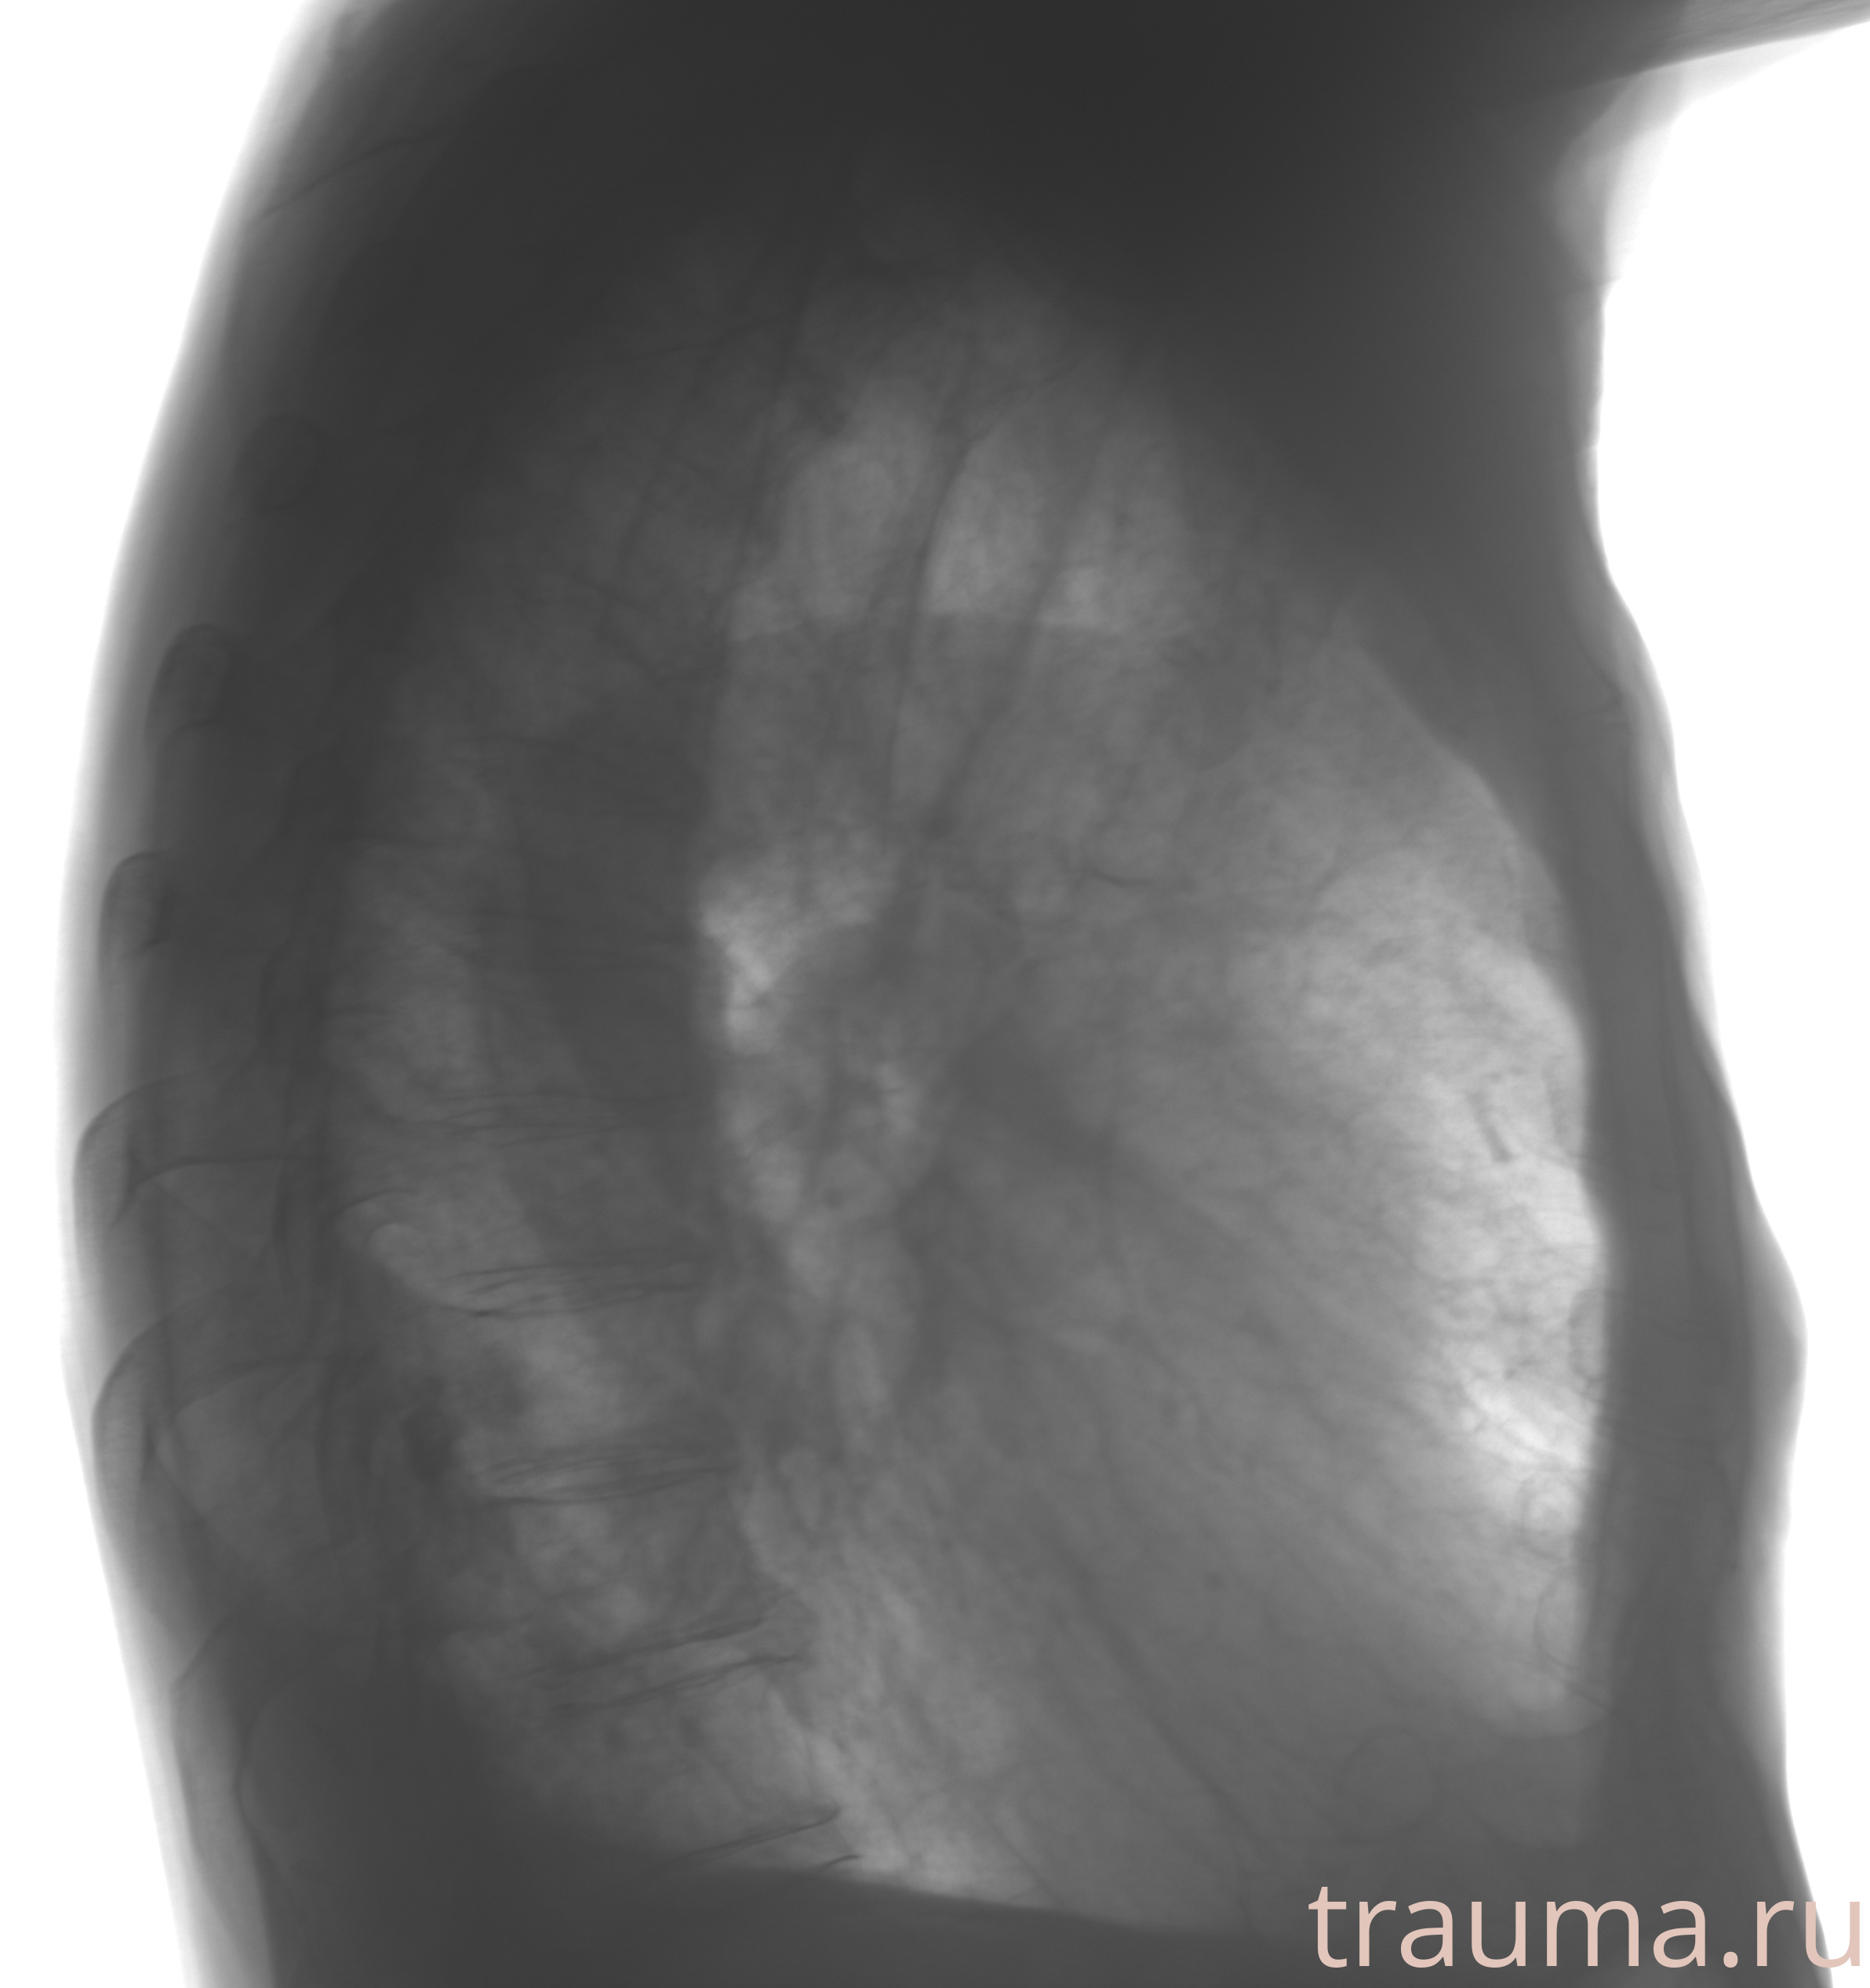

Рентгенограммы

Рентген на дому: по вашему адресу приезжает врач-рентгенолог, травматолог-ортопед с мобильным рентгеновским аппаратом, проводит диагностику травмы или заболевания, делает необходимые рентгенограммы, дает рекомендации по дальнейшему лечению. Получить качественные снимки в домашних условиях возможно благодаря уникальной методике, разработанной МосРентген Центром для института  Склифосовского